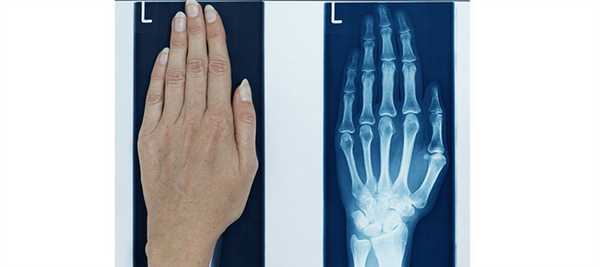

СНИМКИ КИСТИ В ПРЯМОЙ ЛАДОННОЙ ПРОЕКЦИИ

Назначение снимка — изучение скелета кисти в целом, включая запястье, пястье и фаланги.

Укладка больного для выполнения снимка. Больной сидит боком к краю стола. Рука отведена, согнута в локтевом суставе; кисть находится в положении пронации. Пальцы выпрямлены и сомкнуты.

Кассета размером 18Х 24 см расположена в плоскости стола. Ладонь плотно прилежит к кассете.

Средней поперечной линии кассеты соответствует проекция головок пястных костей.

Пучок рентгеновского излучения направлен отвесно на головку III пястной кости (рис. 367).

Информативность снимка. На снимке выявляются дистальные метаэпифизы костей предплечья, рентгеновская суставная щель лучезапястного сустава, запястье, пястные кости и фаланги. Хорошо видны рентгеновские суставные щели мелких суставов кисти.

При правильно подобранных физико-технических параметрах съемки четко видна губчатая структура костей запястья, концов пястных костей и фаланг. В телах коротких трубчатых костей определяются мозговые полости и корковое вещество (рис. 368).